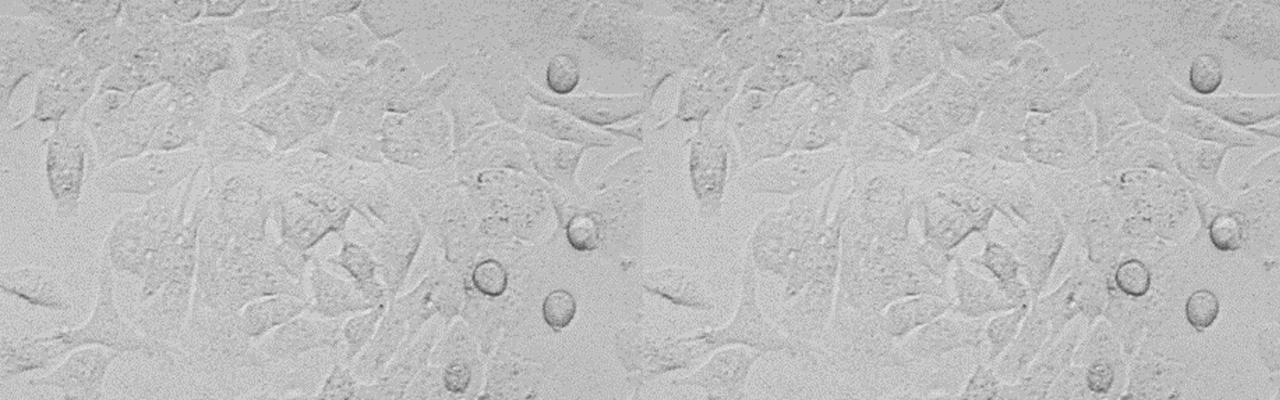

| 细胞全名 | 高转移人肝癌细胞;MHCC97-H |

| 生长特性: | 贴壁生长 |

背景资料:来源于中山医院,用人肝癌细胞株MHCC97-H接种裸鼠,进行3次肺转移筛选,取肺转移瘤建成皮下接种后高度自发性肺转移的肝癌细胞系